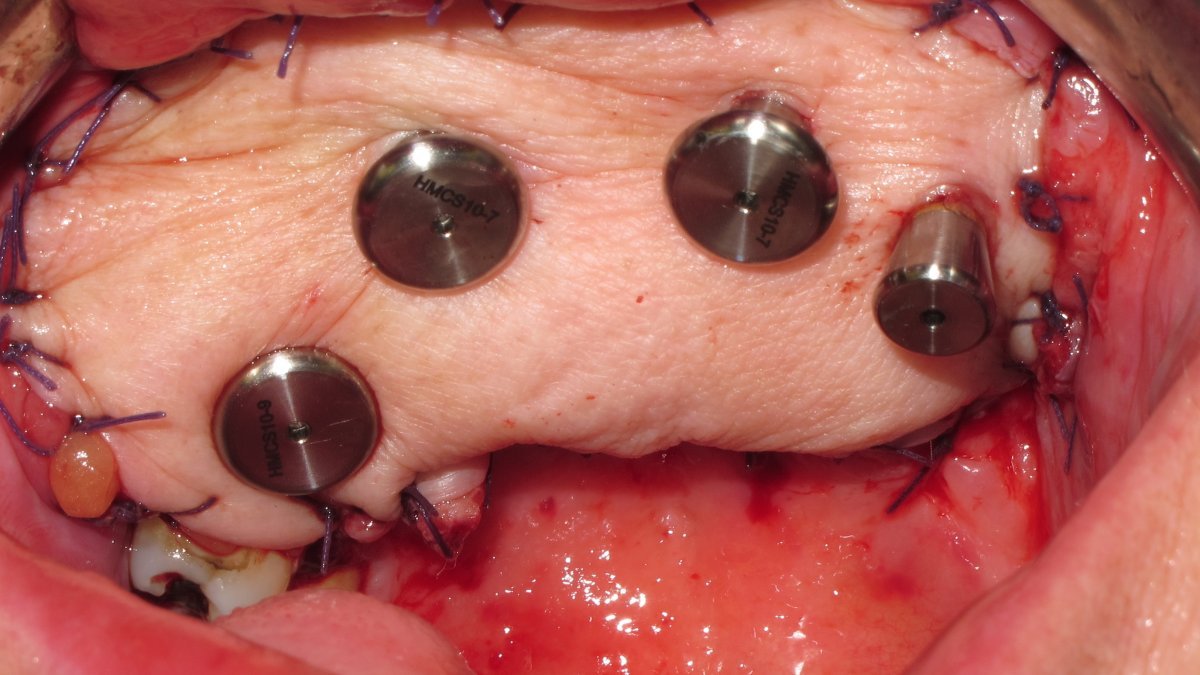

zygomatic implant placement